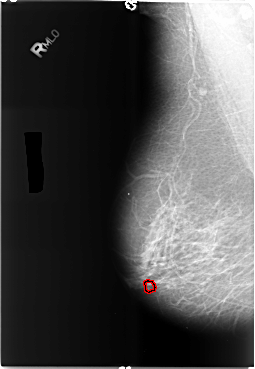

B_3489_1.RIGHT_CC

RIGHT_CC LINES 5920 PIXELS_PER_LINE 4072 BITS_PER_PIXEL 12 RESOLUTION 50 OVERLAY

FILE: B_3489_1.RIGHT_CC.OVERLAY

TOTAL_ABNORMALITIES 1

ABNORMALITY 1

LESION_TYPE CALCIFICATION TYPE PLEOMORPHIC DISTRIBUTION CLUSTERED

ASSESSMENT 4

SUBTLETY 3

PATHOLOGY BENIGN

TOTAL_OUTLINES 1

BOUNDARY